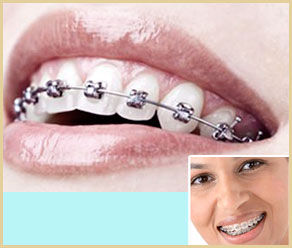

可以龅牙(突嘴)、虎牙、地包天(反颌)、牙列不齐、牙列拥挤、牙列稀疏、前牙开合、深覆合等各种牙齿畸形问题…… 【详细】

成人牙齿畸形矫正,同样可以取得效果,只是成人牙齿矫正对医生来讲更具挑战性,因此会需要相对久一些的矫治时间…… 【详细】

年龄会影响到牙齿的移动和牙齿的生长,牙齿矫正时也是需要考虑年龄关系的,成人与儿童在正畸中存在一些不同。 成年人生长发育已经完成,骨组织的改建能力相对较差,牙齿移动较慢,矫治难度大,疗程长。但成年人一般更能认真配合医生的, 所以矫治效果一样理想,疗程也不会延长很多……【详细】

一般来说,进行牙齿矫正好的时机应该是在我们10—14岁的时候,由于此时我们的牙齿正处于生长的高峰,牙齿移动较快, 颌骨具有相当的生长潜力,正畸不仅可以移动牙齿,还可以诱导颌骨发育,时间短,疗效好…… 【详细】